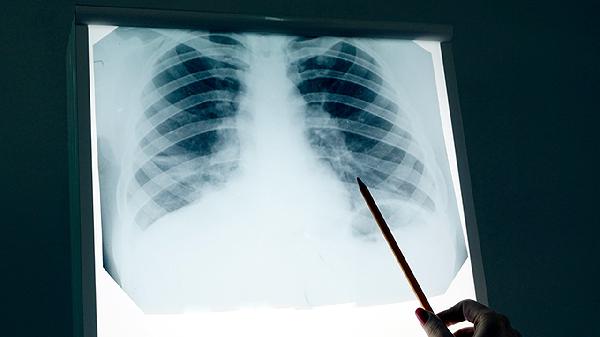

肺癌术后患者通过定期CT复查可以清晰观察到手术区域的变化情况。胸部CT能够显示肺组织修复过程中的结构改变,帮助判断是否存在局部复发迹象。高分辨率CT可检测到毫米级别的微小病灶,对于早期发现肿瘤复发具有重要价值。术后首次CT检查通常在出院前或术后1个月进行,用于评估手术切除范围是否充分以及有无术后并发症。后续随访中CT检查可动态观察纵隔淋巴结状态,及时发现可能出现的淋巴结转移。多层螺旋CT还能重建三维图像,更准确地评估残余肺功能状态。对于接受亚肺叶切除的患者,CT检查可监测保留肺段的代偿性膨胀情况。

肺癌术后复查CT需要关注手术残端有无增厚或新发结节,这些可能是局部复发的征兆。增强CT检查有助于鉴别术后瘢痕组织与肿瘤复发,通过观察病灶的强化特点进行判断。对于接受靶向治疗的患者,CT随访可评估靶病灶的变化情况,为疗效评价提供客观依据。低剂量CT适用于需要长期随访的患者,能在保证图像质量的同时减少辐射暴露。PET-CT可作为CT检查的补充手段,当CT发现可疑病灶但难以定性时,PET-CT能提供代谢信息辅助诊断。术后CT随访发现孤立性转移灶时,可能为患者争取再次手术或局部治疗的机会。